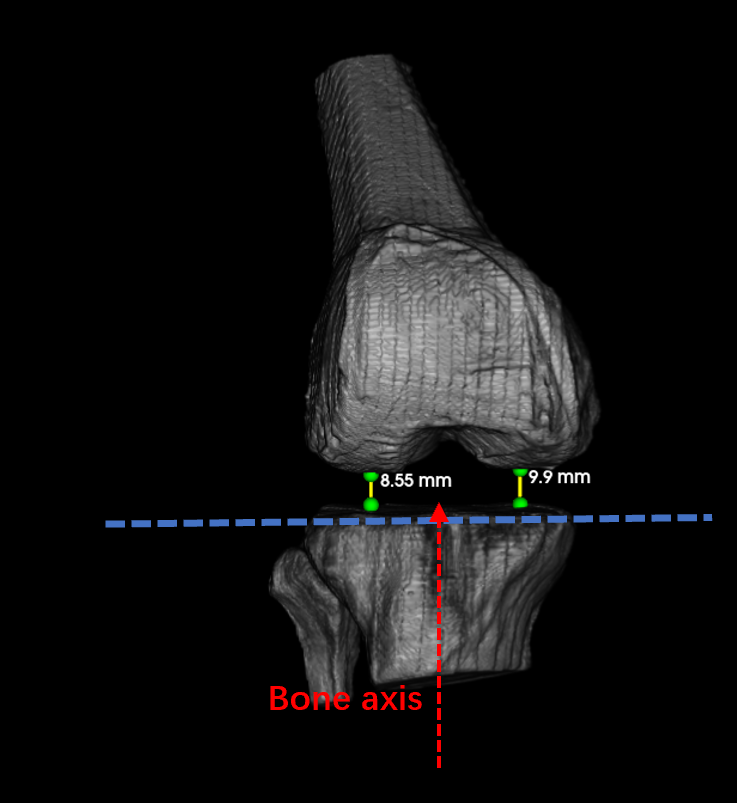

Femorotibial stability was quantified from condylar trajectories projected onto a standardized tibial plateau plane (Figure 11). The femorotibial distance was defined as the perpendicular distance between this plane—aligned with the polyethylene insert in post-TKA cases or 9 mm below the distal tibia in pre-TKA cases—and the lowest condylar points. Variations in medial–lateral trajectory morphology across motion frames provide objective markers of malalignment.

Refer to caption

Figure 11: Illustration of femorotibial joint distances measurement